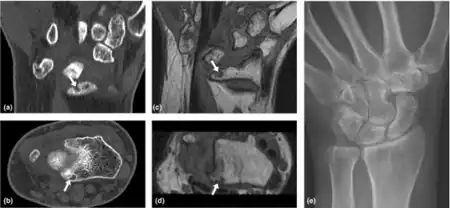

| Loss of Motion-Wrist of rheumatoid arthritis individual a-e) | |

- Loss of motion (symptom): the patient notices that the joint (or many joints) do not move as far as they used to or need to. Loss of motion is a feature of more advanced stages of arthritis including osteoarthritis, rheumatoid arthritis and ankylosing spondylitis.

- Loss of range of motion (sign): the examining medical professional notes that the range of motion of the joint is less than normal. Routine examination by an orthopaedic surgeon or rheumatologist will often pay particular attention to this. The range of motion may be measured and compared to the other side and to normal ranges. This sign is associated with the same causes as the symptom. In extreme cases when the joint does not move at all it is said to be ankylosed.